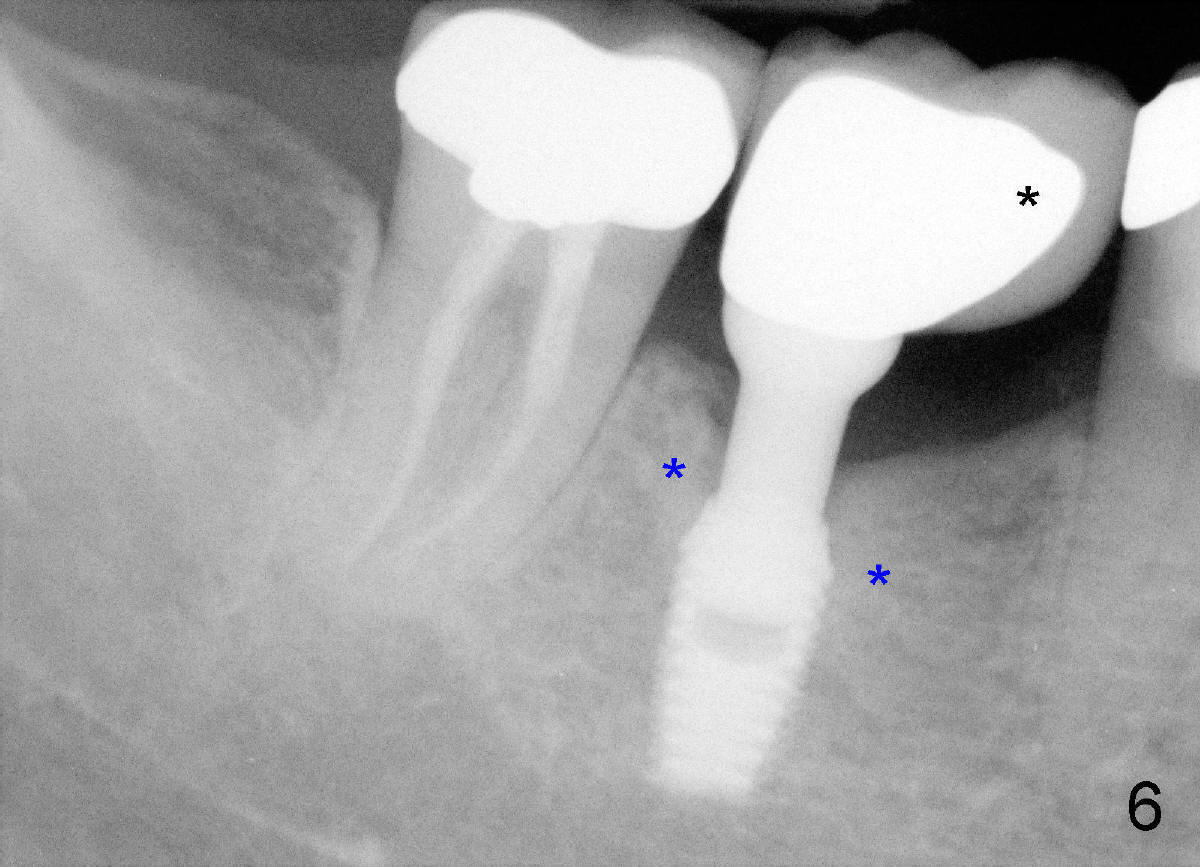

Heavy mastication tends to break not only natural dentition, but also restoration. The crown should be made of full metal, or Zirconium. Or PFM crown should be supported by larger metal framework (Fig.5 black *). This implant is placed off center (in the distal socket). Fig.5 X-ray is taken on the day of PFM cementation. Three years and a half later, there is no porcelain chip (Fig.6), while the bone density around the implant is increased (blue *), as compared to those in Fig.5. In fact the larger metal framework is designed and fabricated by a large dental lab in Florida (Smith-Sterling).